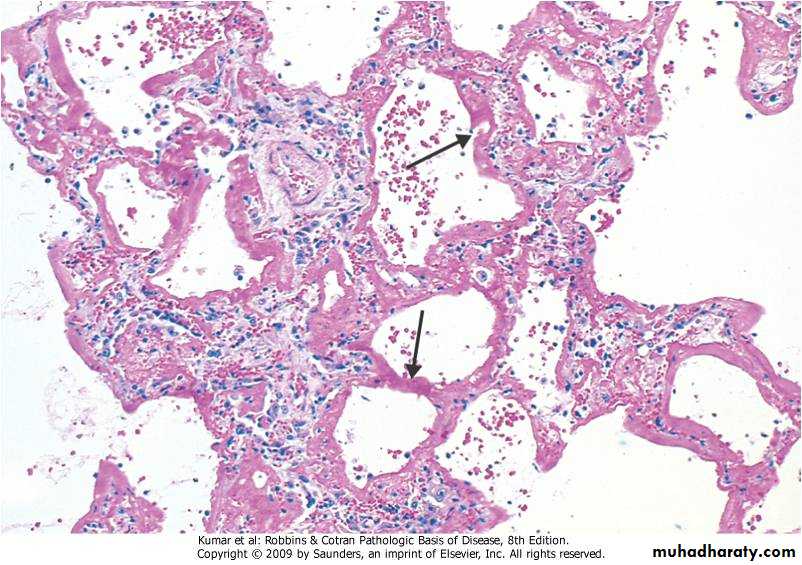

Hyaline Membrane Disease (cont)

Pathology:

Collapse of the alveoli

Respiratory and terminal bronchioles are distended and lined by hyaline eosinophilic materials